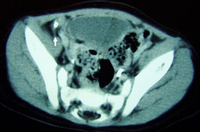

CT scan of a young girl presenting with ovarian torsion. The large pelvic cystic lesion contains calcifications (white arrow) consistent with a teratoma or dermoid cyst

From the collection of Dr KuoJen Tsao; used with permission